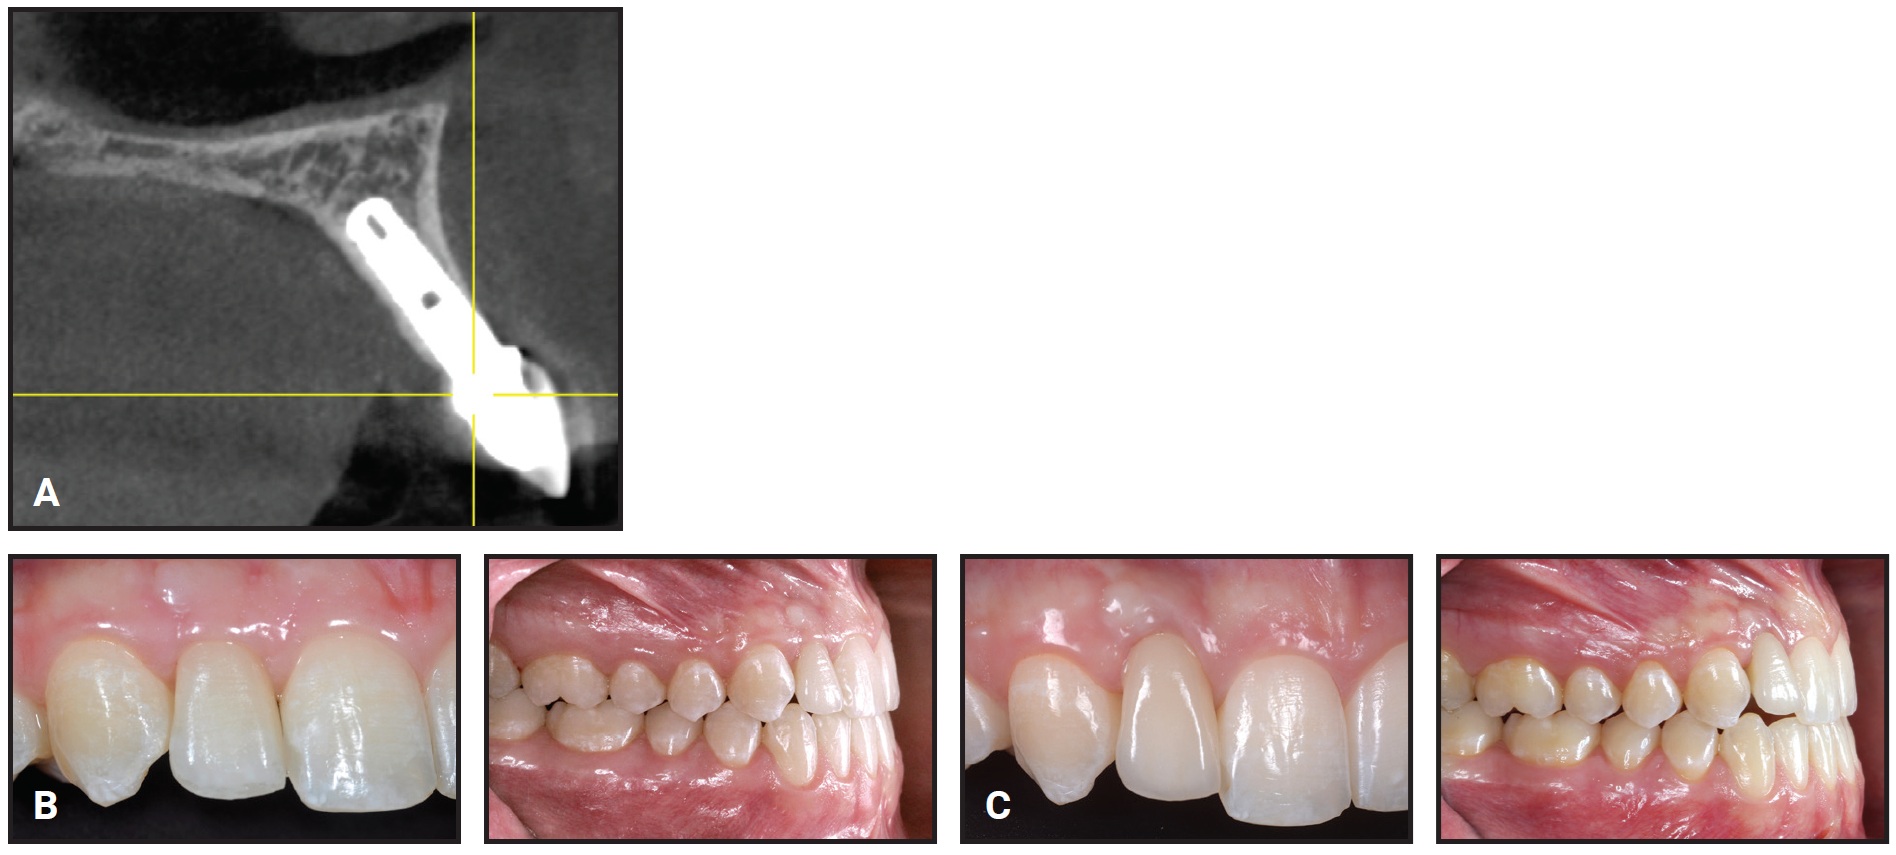

In the IMP group, periapical radiographs were taken with the parallel technique at final crown delivery (baseline, T1) and at follow-up (T2) for evaluation of the crestal bone levels around the implants (Fig. 4). To calculate the change from T1 to T2, the distances from the crown-abutment junction to the first visible mesial and distal bone-to-implant contacts were measured at each time point.45,46 The radiographs were calibrated by adjusting them to the actual length of the various implants using the Dolphin Imaging 11.9 Annotations** program. Calibrated frontal intraoral photographs in maximum intercuspation, centered at the upper dental midline and parallel and slightly superior to the occlusal plane, were used to assess the development of visible infraocclusion between T1 and T2 (Fig. 5). All photographs were taken with a Canon EOS 700D*** digital camera using an EF 100mm f/2.8 Macro USM lens and Macro Ring Lite MR-14 EXII flash.

Fig. 5 Examples of calibrated intraoral photographs used for clinical assessment of visible infraocclusion between baseline (A) and follow-up (B).